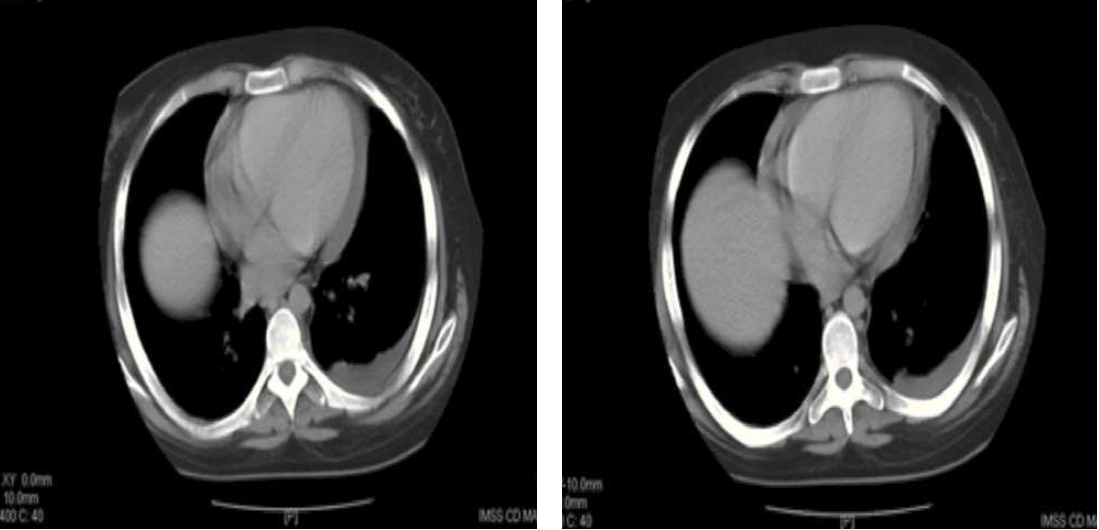

Resultados de laboratorio: hemoglobina 3,7 g/dl, hematocrito 11,4%, volumen corpuscular medio 100 fl, MCH 32,5 pg, MCHC 32,5 g/dl, RDW 26,8%, plaquetas 84,0 × 103, eritroci-tos 1,14 × 106, leucocitos 14,1 × 103, neutrófilos 89%. Se realizó una tomografía computarizada (TC) abdominal (figs. 1-3) que reveló bazo de 15 cm de largo, con múltiples zonas hipodensas de 5 mm de diámetro, derrame pleural izquierdo de 150 ml aproximadamente, derrame pericárdico y líquido libre en el fondo de saco uterino. Se inició tratamiento antimicrobiano con meropenem (1 g c/12 h por vía intravenosa [IV]) y vancomicina (1 g c/12 h IV), y se solicitó evaluación por el Servicio de Cirugía. Al sexto día de estancia, se realizó un hemocultivo que resultó negativo. Tras la valoración quirúrgica, se administraron 6 paquetes globulares y 6 concentrados de plaquetas para corregir la anemia y la trombocitopenia (tabla 1).

Figura 1. Tomografía computarizada que muestra evidencia de líquido libre a nivel pleural izquierdo y pericárdico (flechas blancas); de igual manera, es posible apreciar aumento del tamaño hepático (puntas de flechas).